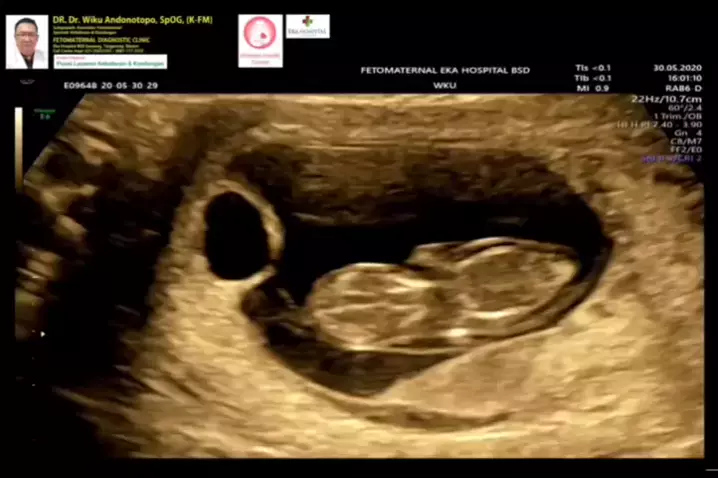

Kehamilan kembar gagal berkembang keduanya... #iufd #fetaldemise #miscarriage #janintakberkembang #keguguran #missedabortion #kembar #kembarnonidentik # # #konsultanfetomaternalekahospitalbsd #usgfetomaternalekahospitalbsd #fetomaternalekahospitalbsd #fetomaternalpontianak #drwikuandonotopo #polikandunganekahospitalbsd #spog #indonesia